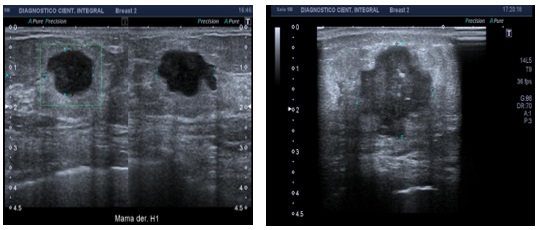

Características radiológicas del cáncer de mama triple negativo en mamografía

Se han llevado a cabo numerosos estudios en distintos países, en especial en Asia, para analizar las características de imagen del CMTN. Estos estudios han revelado que en mamografías la presentación más común suele ser en forma de MASA o NÓDULO, con tasas de hasta el 64%. La mayoría de estas masas carecen de calcificaciones. En contraste, las microcalcificaciones, que son una presentación común en cánceres dependientes de hormonas, se observan en un porcentaje mucho más bajo, alrededor del 5,7%.(19, 6)

En otros estudios se describe que el CMTN puede quedar oculto en mamografía o, en su defecto, presentar características morfológicas benignas, como nódulos sólidos, únicos, de contornos lobulados o asimetrías focales no asociadas a microcalcificaciones.(5, 19, 22, 23, 24, 25, 26, 27)

A menudo, se observa que en mamas con aumento de la densidad categorizada según el American Collage Radiologist como (ACR D), puede verse dificultada la detección del tumor.(20, 22, 23, 24)

Características mamográficas del CMTN

Los resultados de las características mamográficas en nuestra población con CMTN (n = 17) se describen de la siguiente manera: la mayoría presentó un tejido fibroglandular ACR B (n = 10), lo que equivale al 60% de la muestra total. Le siguió un ACR A (n = 3). En cuanto a la descripción de los nódulos, se reportaron como ovalados en el 70% de los casos, con márgenes circunscritos en el 47%. Además, se observó que eran hiperdensos en el 76% de los casos y no presentaban calcificaciones asociadas (100%). No se encontró evidencia de adenopatías axilares ni lesiones asociadas mediante este método diagnóstico.

Anexo 1. Imágenes mamográficas de CMTN